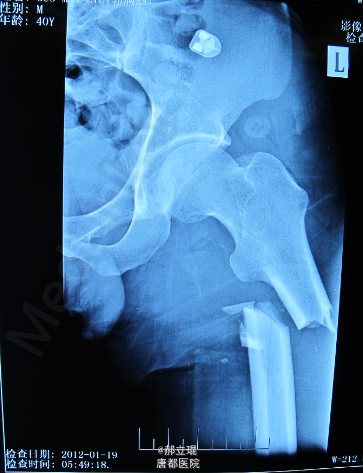

骨折 股骨粗隆下骨折

左髋部疼痛,活动受限,左足跟叩击痛阳性, X片提示: 左股骨粗隆下骨折

左股骨粗隆下骨折, 使用锁定钢板固定.

随访4月骨折愈合良好, 患肢功能良好.